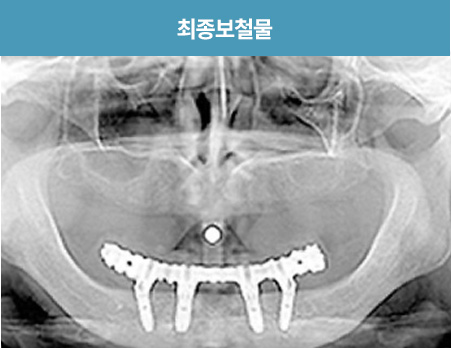

I      올온포 풀아치 임플란트 사례      I

치료 기간 : 2021.03.12 ~ 2021.08.25